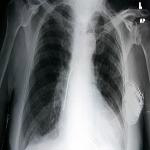

A pacemaker is a small device that doctors place in people with an abnormal heartbeat. If a heart beats too slowly, the pacemaker will use electrical signals to help set a normal rate. Some devices include a defibrillator, which gives a shock if the heart beats too fast.

Pacemakers may be permanent or temporary. But one thing is sure. Developing countries need more of them as more people get heart disease.

But are used pacemakers safe? Doctor Baman studied medical reports about the safety of pacemakers that were being reused in small studies.

TIMIR BAMAN: "We found that there's no real difference in device infection or device malfunction when you compare it to new pacemaker implantation."